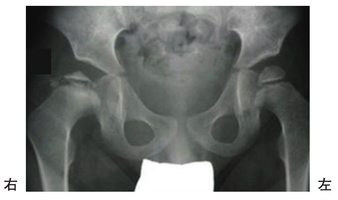

第56回 午前 作業療法士実地問題

アテトーゼ型脳性麻痺児の食事の様子を図に示す。スプーンを口に近づけると図のような姿勢になってしまう。この児に出現している原始反射はどれか。